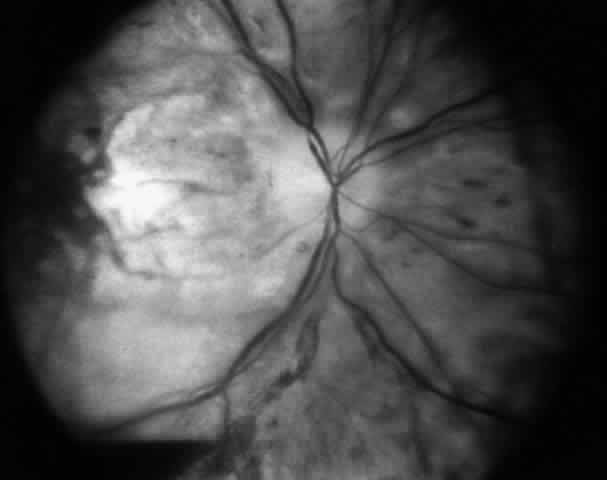

Absolute contraindications include any procedure that carries a significant risk of loss of vision. For example, if there is a significant risk of anterior segment ischemia, or if ischemia occurred in the patient previously, and alterations in surgical technique will not reduce this risk, surgery is inadvisable. If correction of a problem requires surgery on the sound eye of a patient with monocular blindness, and the patient cannot accept the remote risk of loss of vision, surgery is contraindicated (Fig. 6). Reoperation should not be attempted in situations wherein the surgeon is unable to understand the causes of the motility problem or is unable to formulate a surgical plan that has a reasonable chance for successfully achieving the desired alignment. Surgical risks and morbidity are also probably not justifiable in some cases where the patient has a very limited life expectancy. As for any surgery, unacceptable anesthetic risk is a strict contraindication to reoperation.

Fig. 6. Loss of vision after strabismus surgery is very uncommon. This 45-year-old woman had received orbital radiation prior to her strabismus surgery. The surgery was performed with retrobulbar anesthesia. Four days after the operation, vision was decreased from 20/20 to light perception. It is presumed that there was injection of the anesthetic into or around the optic nerve that caused compromise of the central retinal artery. The fundus photograph was taken 4 days after the procedure.